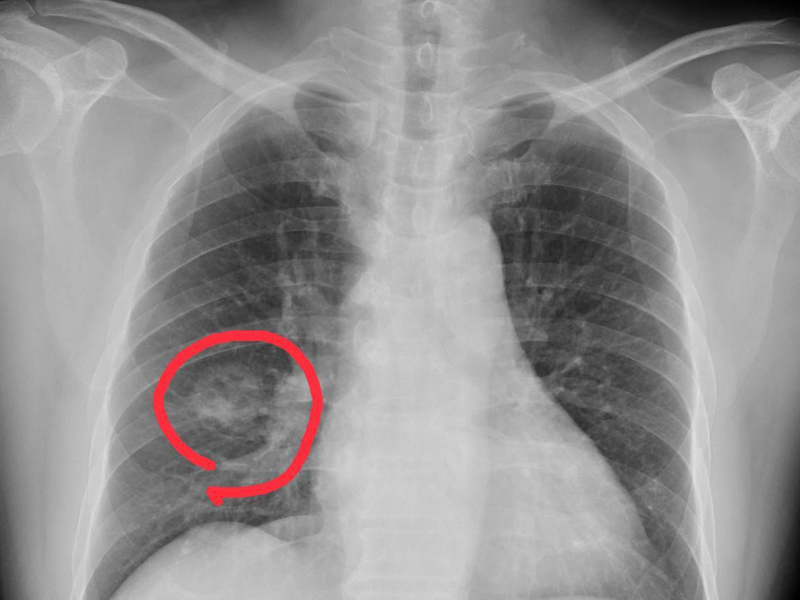

4. 腫瘤

雖然比例不足 10%,但如鼻咽癌或鼻竇癌,可能以血性鼻水或痰為初期症狀,出血量雖少卻不可輕忽。